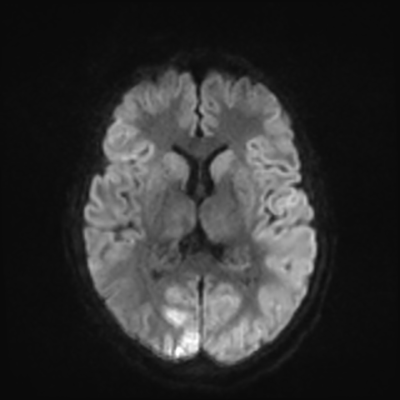

MRI brain (DWI)

You can clearly see diffuse cortical and basal ganglia diffusion restriction, and that of his deep cerebellar nuclei as well. The right occipital lobe abnormalities are a little more prominent, but then you remember that he is known to have had a right occipital stroke weeks ago.